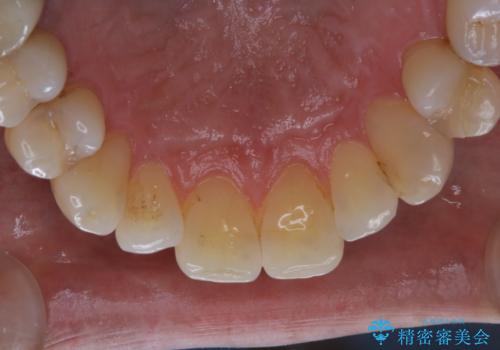

- PMTCでのメンテナンスを定期的に行っている方です。PMTC30分コースを行いました。

日々の磨き残しなどをそのまま放置すると、細菌が固まり硬い歯石になります。

歯石になってしまうと、とても硬く、歯ブラシで取り除くことが出来なくなります。

よって、歯科衛生士による専門的なクリーニングを定期的に行うことがとても大切です。

メンテナンスの間隔は個人差がありますが、基本的には2~3カ月に一度行うことをおすすめしています。